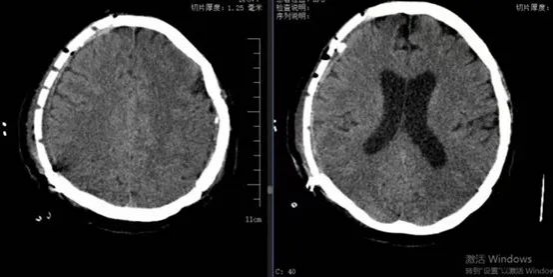

患者女性,59歲,2024年4月3日因外傷后致右側(cè)額顳頂部急性硬膜下血腫伴腦疝形成,急診行右側(cè)開顱血腫清除術(shù)+去骨瓣減壓術(shù)。術(shù)后患者轉(zhuǎn)危為安,恢復(fù)良好出院。但右側(cè)頭部遺留顱骨缺損,不僅影響美觀,而且會給患者帶來不安全感,甚至引起顱骨缺損綜合征、腦萎縮、外傷性癲癇等多種不良后果。

此次患者來到我院,想通過進一步治療解決顱骨缺損問題。神經(jīng)外科團隊仔細評估了患者病情并制定了詳細的手術(shù)方案。術(shù)前進行了頭顱CT掃描,利用計算機構(gòu)建出患者顱骨缺損三維重建圖。